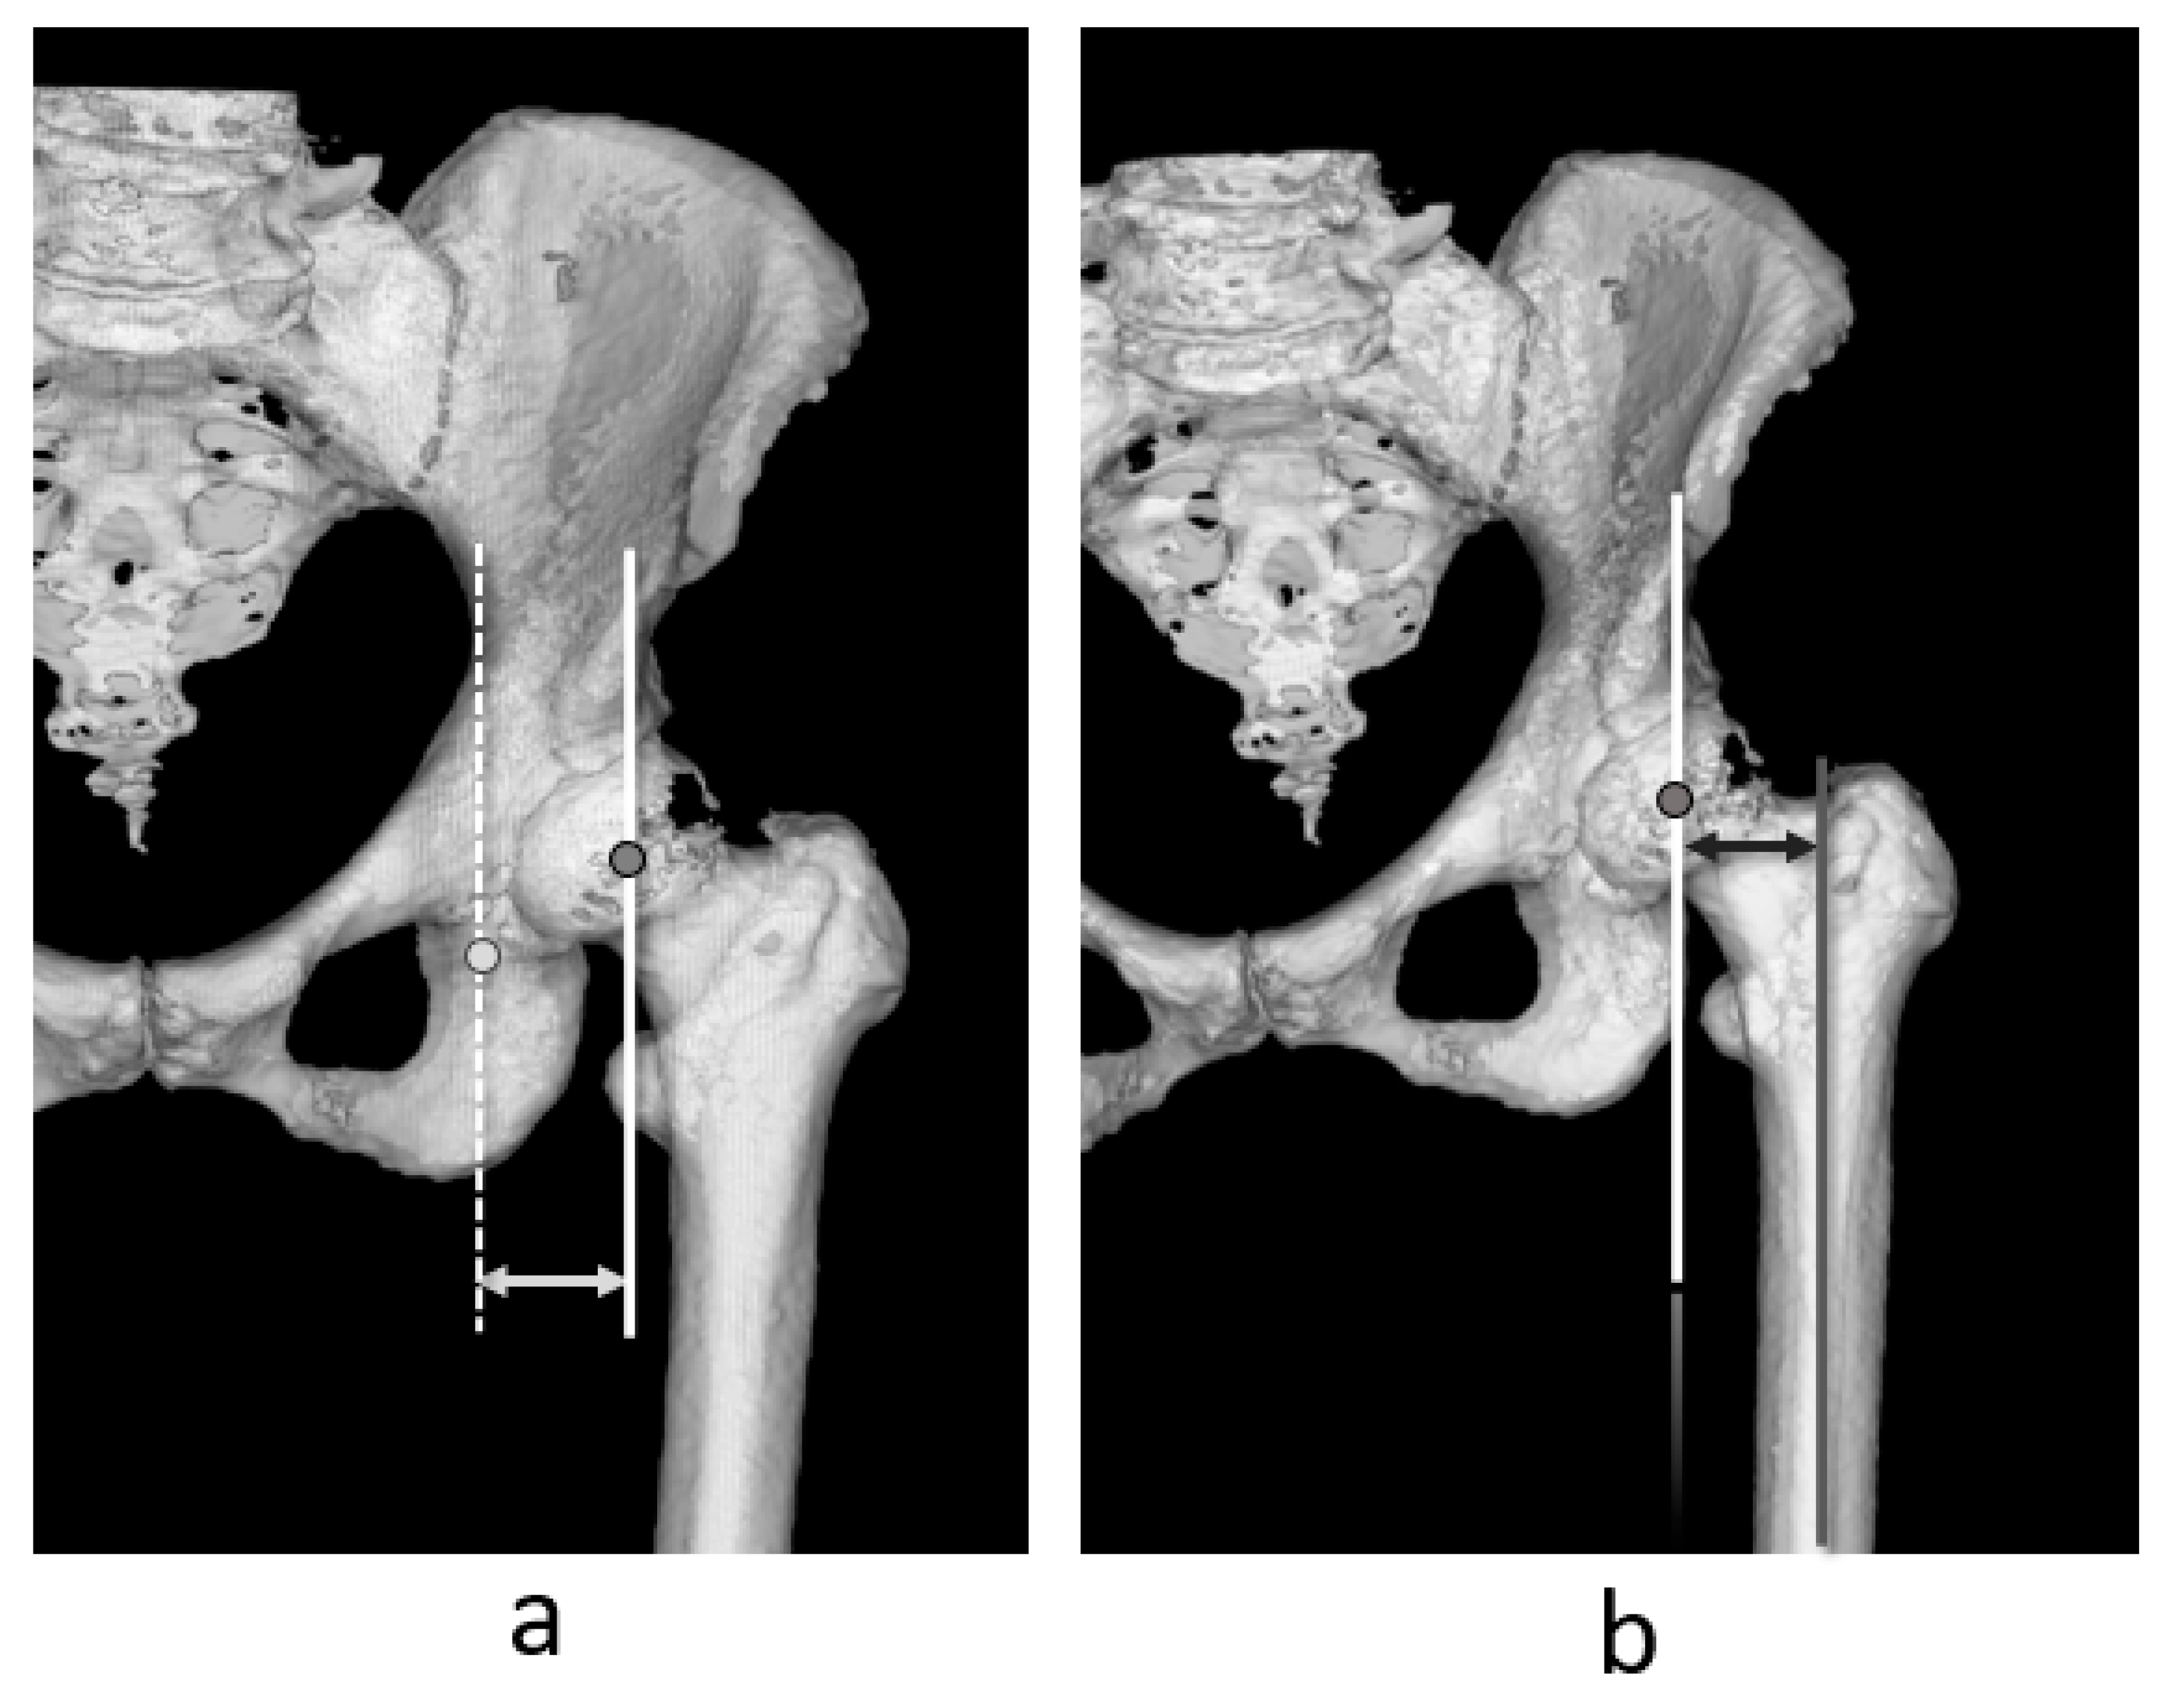

2.3. Measurement